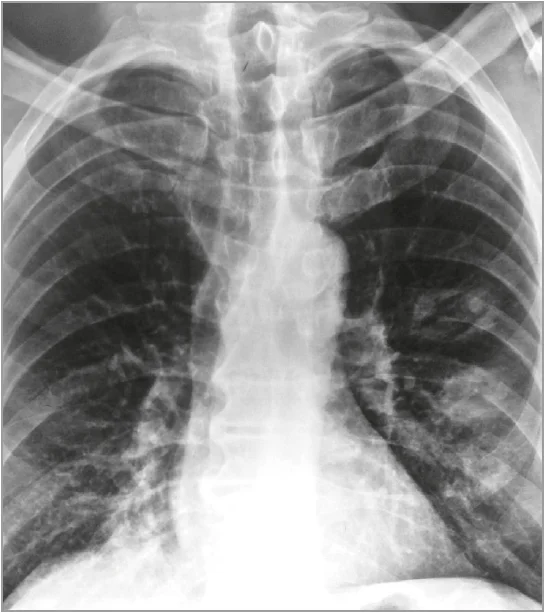

Інструментальне обстеження. Рентгенографія органів грудної клітки 23.12.2023: інфільтрація легеневої тканини в проєкції S10 зліва; права легеня не змінена; серце й аорта в нормі (рис. 3). Повторна рентгенографія 15.01.2024: у лівій легені консолідовані округлі вогнища, не можна виключити деструкції; в правій легені над діафрагмою зниження пневматизації через інфільтративні зміни, корені структурні, правий корінь унизу тяжистий, синуси вільні, діафрагма чітка.

Рис. 3. Рентгенографія органів грудної клітки військовослужбовця на 5-й день після контакту з невідомою отруйною речовиною на бойових позиціях